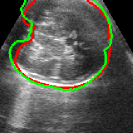

As mentioned in Sec. 3.2, it is crucial for our brain extraction network to work consistently regardless of the orientation of the brain within the US volume. This can be qualitatively observed in Fig. 3, which shows the outline of the brain-extraction prediction and the corresponding ground-truth, in red and green respectively, for six different 3D US volumes. These volumes have been selected to demonstrate the amount of variation between each scan, with the position of the fetus inside the mother as well as the position of the brain in respect to the scan varying drastically from case to case.

As shown in Fig. 3 , the network’s prediction is remarkably close to the ground-truth, regardless of the position of the brain in the volume. It also manages to accurately predict the location of the brain when this is partially obscured either by the cropping or the shape of the ultrasound beam.